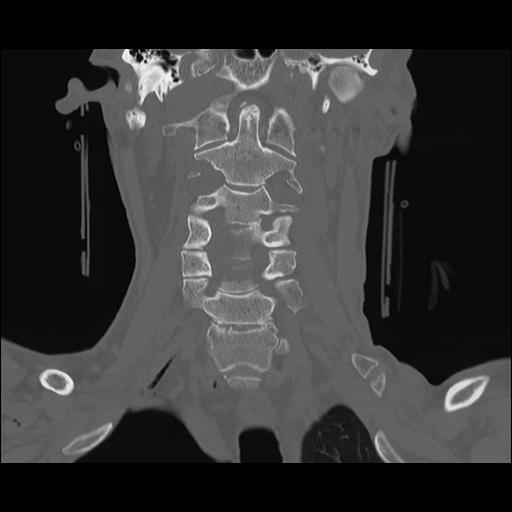

16 HUESO,,Coronal,2.000,HUESO,Coronal,